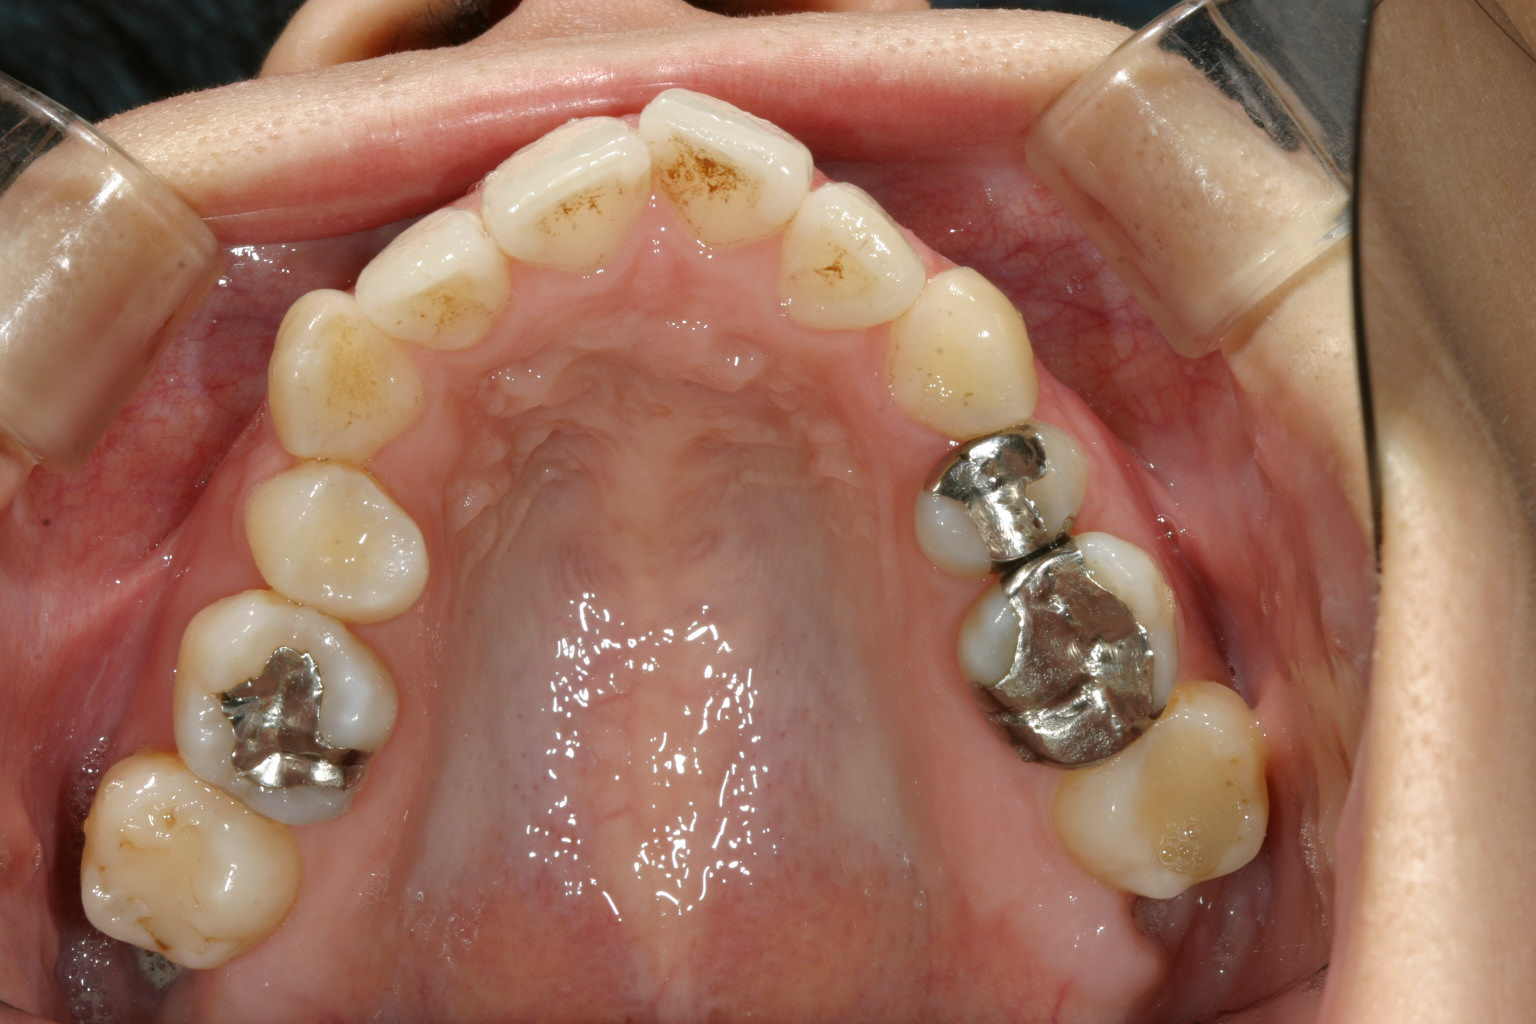

特に上顎のアーチが狭くなり先が尖って、それに合わせて下顎も叢生が再発していました。

この様な後戻りケースはインビザラインの最適な適応症で患者様が時間守って使用して頂ければ難なく改善致します。